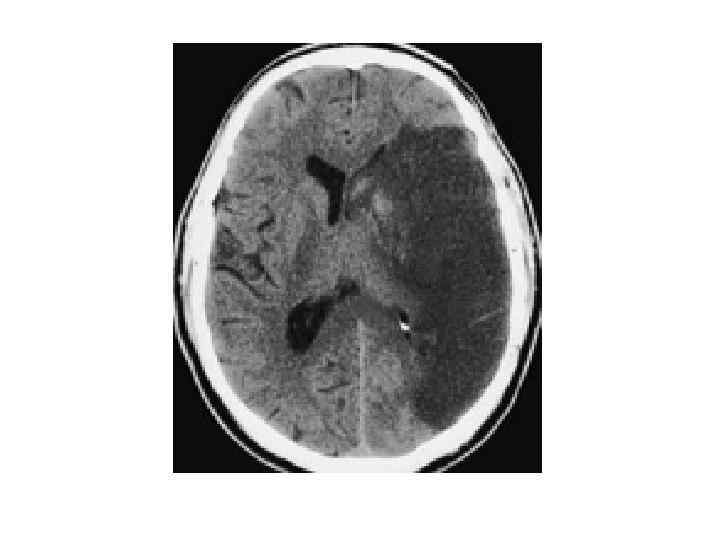

Хроническая ишемия головного мозга и лейкоареоз: симптомы и лечение